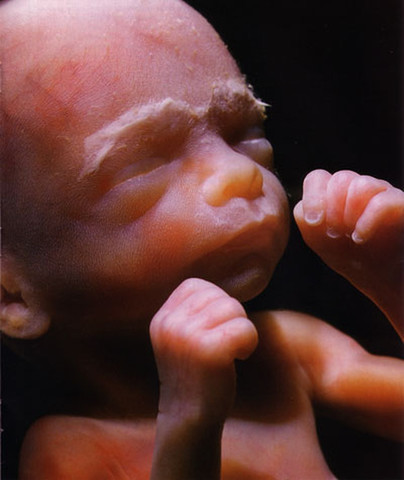

• Semanas 9 a 12

Semanas 9 a 12

Los párpados se cierran y no se vuelven a abrir casi hasta la semana 28

La cara está bien formada

Las extremidades son largas y delgadas

Los genitales aparecen bien diferenciados

Los glóbulos rojos se producen en el hígado

El tamaño de la cabeza corresponde casi a la mitad del tamaño del feto

El feto puede empuñar los dedos

Aparecen los brotes dentarios

• Semanas 13 a 19

Semanas 13 a 19

El feto tiene una longitud cráneo-caudal de unas 3 pulgadas (8 cm). A veces, ya se puede ver el sexo del feto mirando los órganos externos en un ultrasonido.